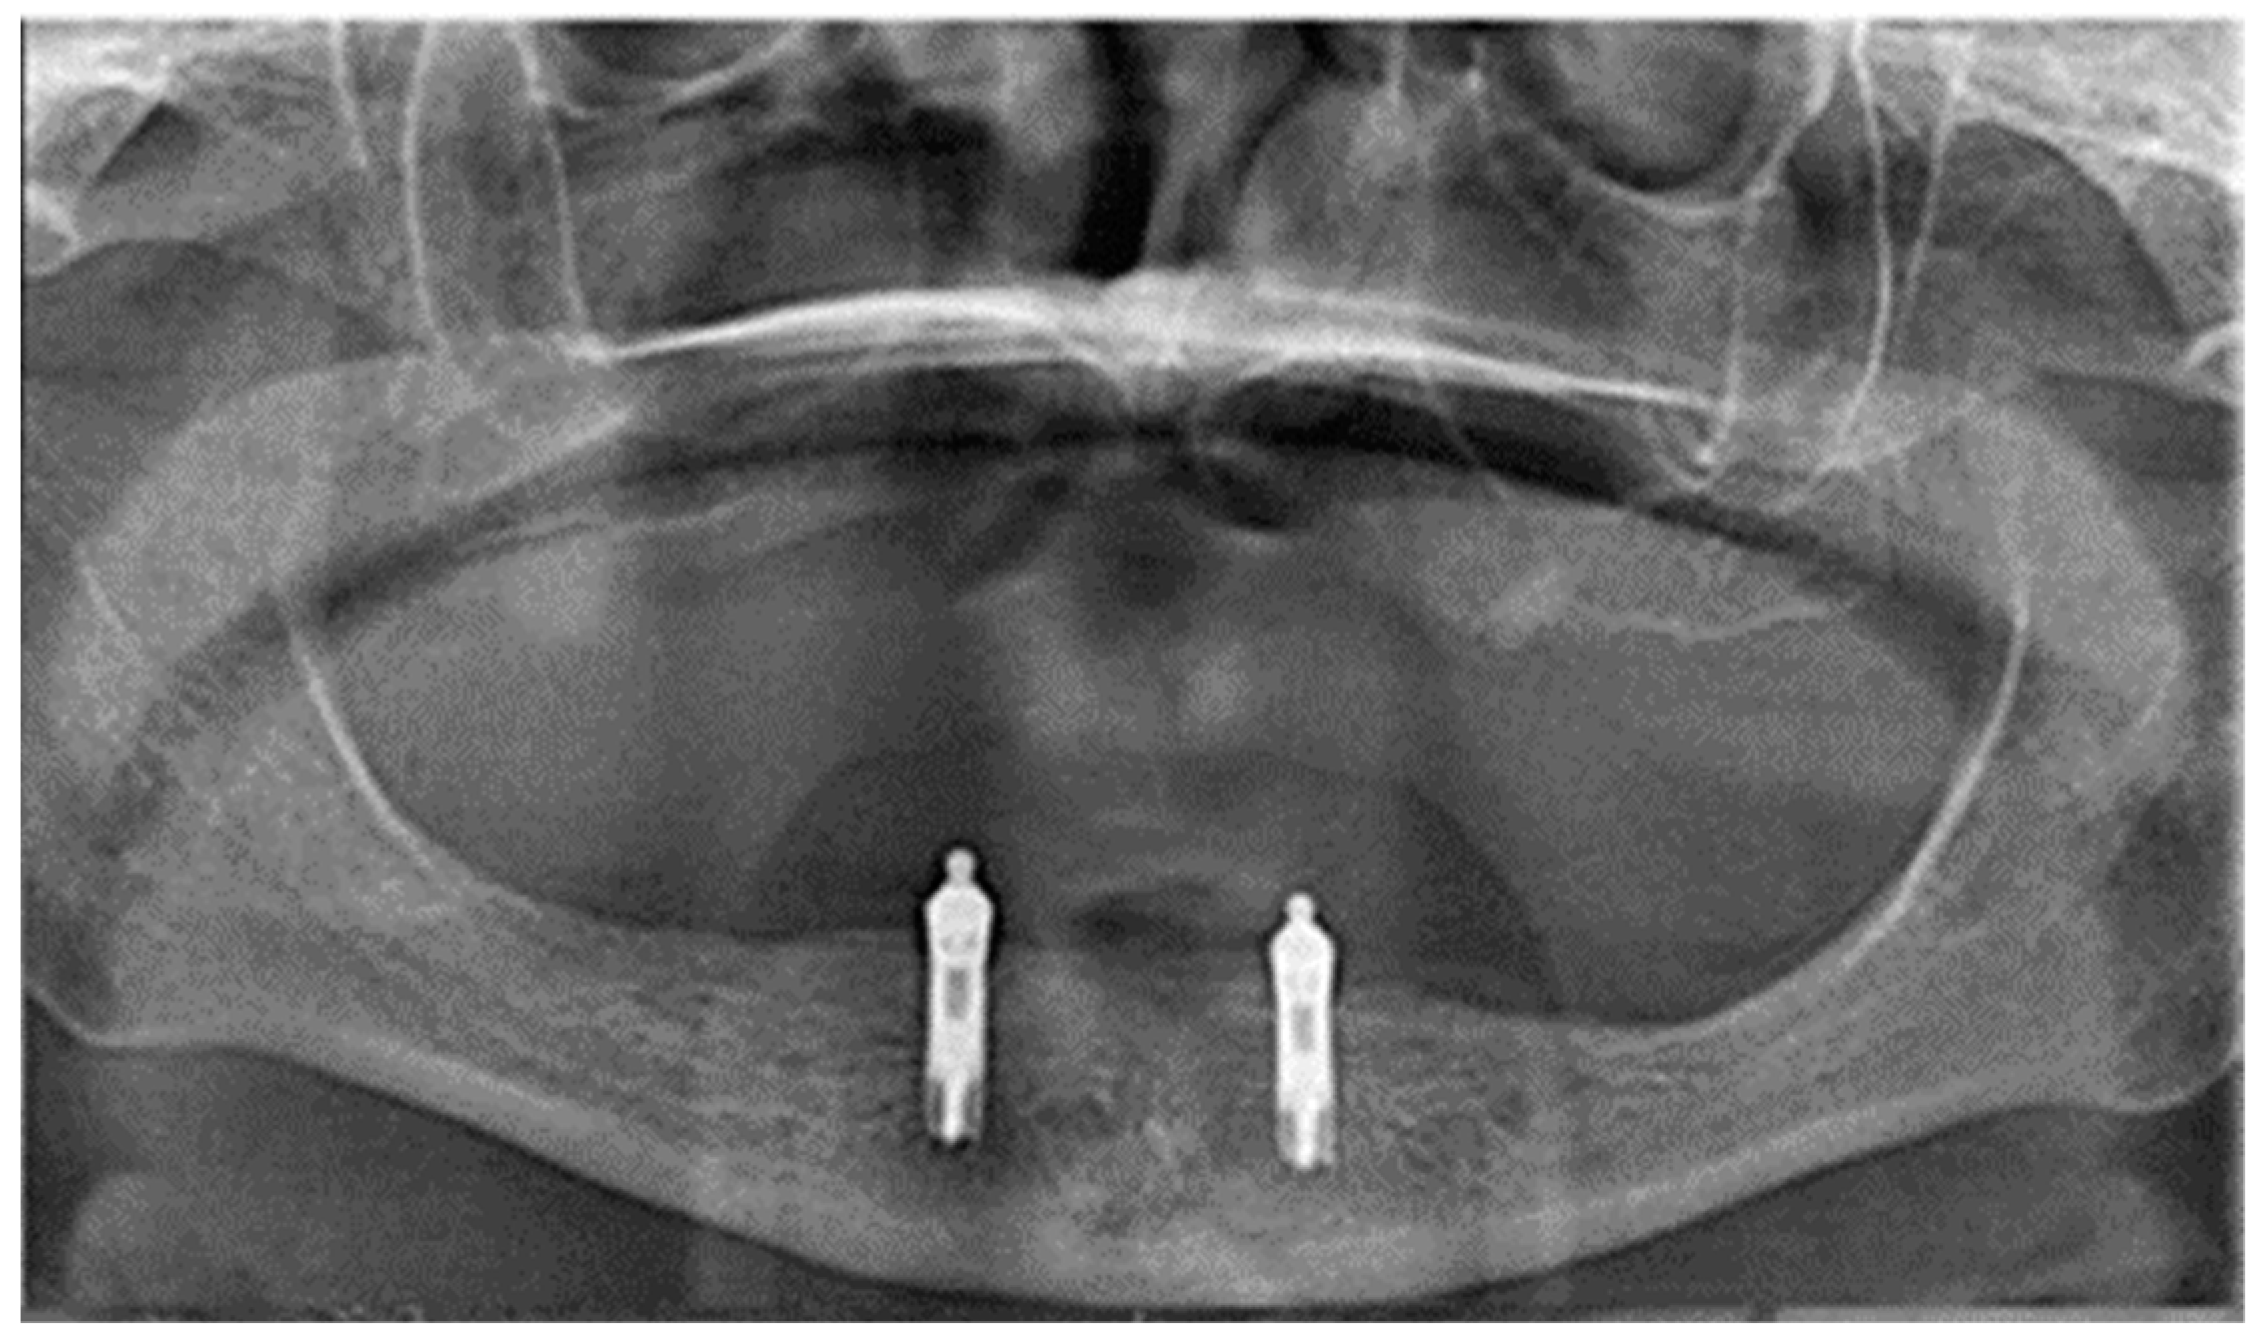

2.2. Surgical Treatment

2.3. Prosthetic Treatment